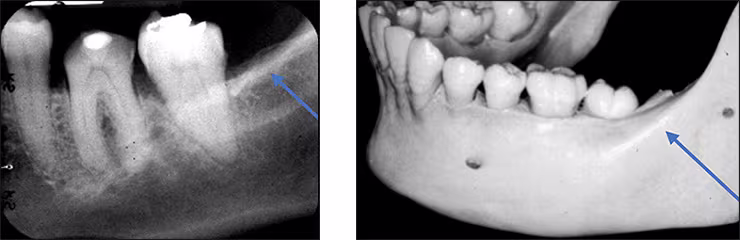

External oblique ridge – The external oblique ridge or line is the bony anterior border of the ramus located on the outer aspect of the mandible. This ridge has a downward diagonal course and is seen on most mandibular molar periapical images and molar bitewings. It is more prominent and appears more frequently than the internal oblique ridge which will be discussed next. This bilateral radiopaque landmark gives the mandible and the dentition a smile appearance.

Internal oblique ridge - The internal oblique ridge is the bony ridge found bilaterally on the lingual aspect of the posterior mandible. This radiopaque ridge is variable in its appearance ranging from highly defined to barely visible. When recorded on molar periapical images, it runs parallel to but below the external oblique ridge. The internal oblique ridge is sometimes referred to as the mylohyoid line.

Submandibular fossa – The submandibular fossa is a depression in bone on the lingual aspect of the posterior mandible. The fossa is located bilaterally below the internal oblique ridge or mylohyoid line. This concavity is where the submandibular salivary gland rests. The submandibular fossa presents as a diffuse bilateral radiolucency typically with few trabeculae. It can appear unusually radiolucent, enticing the novice clinician into thinking a bony lesion is present. The submandibular fossa is recorded on premolar and molar periapical images. This structure is also referred to as the submandibular gland fossa or mandibular fossa.